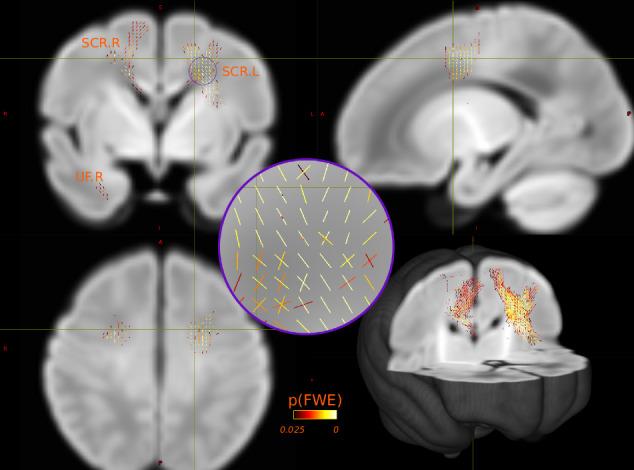

Increasing lines of evidence suggest white matter (WM) structural changes associated with autism can be detected in the first year of life. Despite the condition having high heritability, the relationship between autism common genetic variants and WM changes during this period remains unclear. By employing advanced regional and whole-brain fixel-based analysis, the current study investigated the association between autism polygenic scores (PS) and WM microscopic fibre density and macrostructural morphology in 221 term-born infants of European ancestry from the developing Human Connectome Project. The results suggest greater tract mean fibre-bundle cross-section of the left superior corona radiata is associated with higher autism PS. Subsequent exploratory enrichment analysis revealed that the autism risk single nucleotide polymorphisms most associated with the imaging phenotype may have roles in neuronal cellular components. Together, these findings suggest a possible link between autism common variants and early WM development.

越来越多的证据表明,与自闭症相关的白质(WM)结构变化在生命的第一年就可以被检测到。尽管这种疾病具有高度遗传性,但在此期间自闭症常见基因变异与WM变化之间的关系仍不清楚。通过采用先进的基于体素的区域和全脑分析,本研究调查了来自正在进行的人类连接组计划的221名欧洲血统足月出生婴儿的自闭症多基因评分(PS)与WM微观纤维密度和宏观结构形态之间的关联。结果表明,左额上回放射冠束平均纤维束横截面积越大,自闭症PS越高。随后的探索性富集分析表明,与成像表型最相关的自闭症风险单核苷酸多态性可能在神经元细胞成分中起作用。总之,这些发现表明自闭症常见变异与早期WM发育之间可能存在联系。